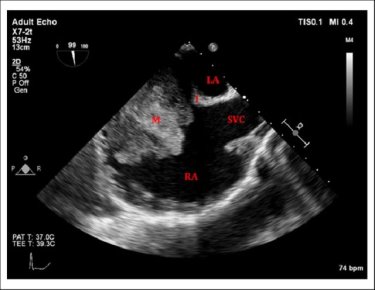

Bicaval view is an Important TEE view to visualize, the LA, IAS, and right atrium. I used to have some trouble getting oriented to this view. Hence this post. It is obtained in the 90-120 degree view at the mid esophageal position. Imagine the patient is lying on his left side and the probe comes from above down between the spine and heart to the LA from within the esophagus. This is the best view to see IAS in the profile.(Subcostal TTE can also do it) Note how the LA hugs the right atrium which is actually an ill-defined (In TEE I mean) common meeting point of both IVC and SVC. Also important is the relationship of RUPV with SVC & the horizontally running RPA sitting right over the top of LA.

The relationship between RUPV and SVC is crucial in device closure of large ASD, especially in sinus venous defect.

Very useful in ASD rim morphology especially in the posterosuperior rim.

Delineates clearly the defect boundaries in SVC ASD.

Sinus venosus defect: Image source not known. Thanks to the creator.